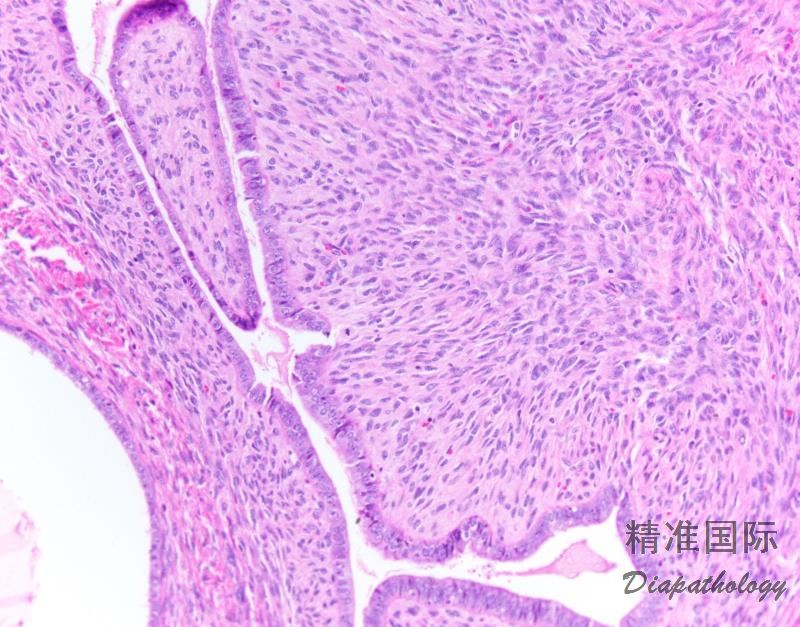

肿瘤内遍布管状腺体和裂隙样腔隙,衬覆上皮的乳头状间质由表面突入囊腔,导致叶状肿瘤样外观;

表面上皮和腺上皮通常类似增殖期或萎缩子宫内膜上皮也会出现许多其他类型的上皮,包括分泌性上皮、黏液性上皮、鳞状上皮和透明细胞;

上皮通常形态温和,但偶尔也会见到增生性,甚至非典型增生性上皮;

腺体周围间质细胞丰富是腺肉瘤的特征性表现,几乎每个病例都可见细胞丰富的袖套样间质围绕腺体或在表面上皮下方形成富于细胞的间质条带,至少局部如此;